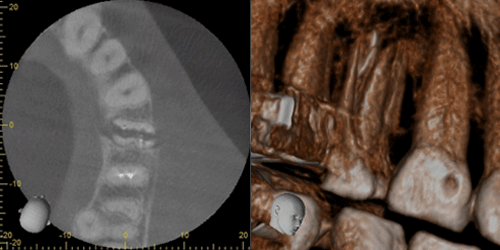

インプラント治療とCT

インプラント治療では、術前の骨の状態(質や厚み、高さ、形態など)を正確に判断ができるので、切開や剥離をしない手術など に対して、すぐに判断が可能です。歯科用CTでの撮影画像をもとに、的確な治療計画を立てることは、安心・安全な治療への第一歩です。